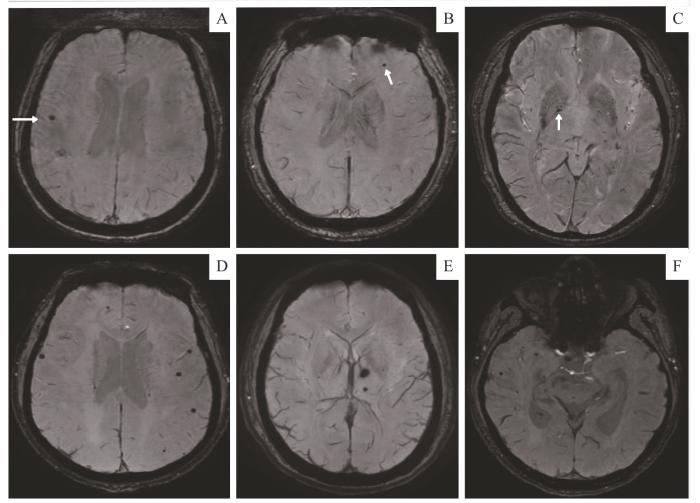

2例患者不同脑区微出血灶的SWI图像

Note: A‒C. A 36-year-old female with ESRD who had undergone hemodialysis for 3 years had a few lesions in the right frontal lobe proximal cortex (A), the left frontal subcortex (B) and the right globus pallidus (C). The white arrows show the lesions in each brain region. This patient had no cognitive impairment, with a MoCA score of 28. D‒F. A 41-year-old male with ESRD who had undergone hemodialysis for 1.5 years showed multiple scattered CMBs in the frontal, temporal and occipital lobe (D and F), as well as in the left basal ganglia (E). This patient had cognitive impairment, with a MoCA score of 17.

Fig 2

SWI images of CMBs in different brain regions in two patients